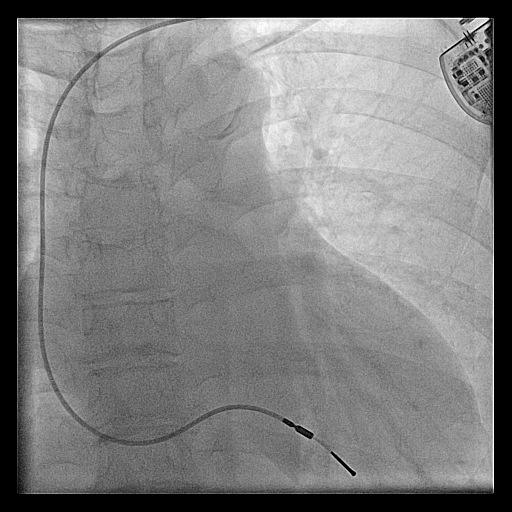

Venogram

• Difficult puncture

• Pre-existing leads

• 10-15 ml of contrast from ipsilateral arm

• Management of stenosis

Puncture with venogram